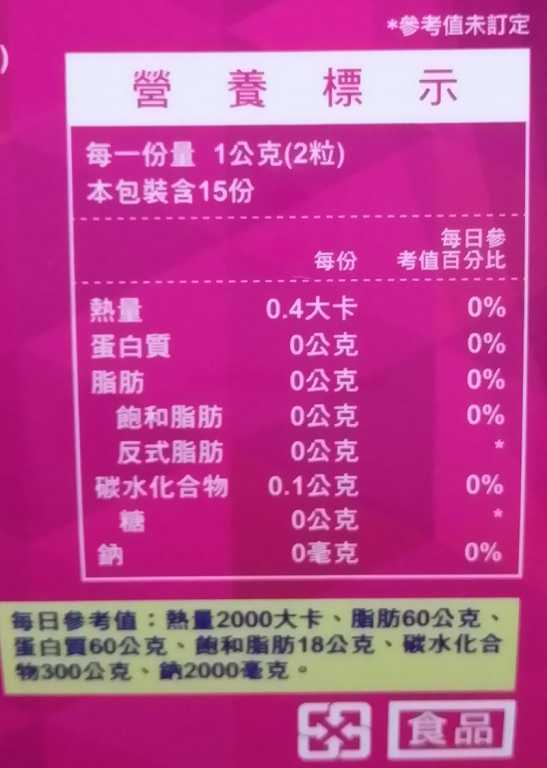

Supercut塑魔纖立塑膠囊的成分有:瓜拿那萃取粉、肉桂萃取粉、辣椒萃取物(唐辛子)、吡啶甲酸鉻、番瀉葉粉末、玉米澱粉、氧化鎂、二氧化矽。

食用方式:早晚餐前30分鐘各1粒,每日不超過2粒。(多食無益)